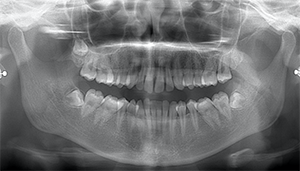

左下の歯茎が腫れている親知らずの症例

- 抜歯前写真(レントゲン、CT等)

左下の親知らず周囲歯肉が腫れていました。

また、手前の歯との間で虫歯もできていました。

3分割して抜歯しました。

| 年齢 | 20代・女性 |

|---|---|

| 主訴 | 左下の歯茎が腫れている |

| 適応するプラン | スタンダード親知らず抜歯プラン |

| 親知らずの生え方 | 歯茎から少し頭が出ている |

| 抜歯時間 | 15分 |

| 費用 | 約7,000円 |

| 抜歯内容 | 下顎の親知らずの抜歯希望の患者様です。 智歯周囲炎となっており、初診時では麻酔が効きづらい旨をお話しし、初診時は抗生物質をお出ししました。1週間後、ある程度歯肉の炎症がとれたことを確認して抜歯を行いました。 麻酔を行い、遠心(親知らずの奥側)歯肉と、手前の歯の頬側の歯肉を切開しました。 歯茎を開いて、手前の歯と引っかかっている部分をカットしました。 その後、骨からでている歯冠部(頭の部分)をカットしました。 その後へーベルで歯根(骨に埋まっている部分)を脱臼し、抜歯を終えました。 切開した歯茎を3針縫って、治療終了となりました。 歯茎を切ったため、3日ほど腫れぼったい感じがあったようですが、痛みはほとんどなく、治癒に向かいました。 |